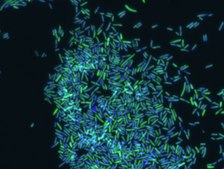

Fluorescent In Situ Hybridization technique (FISH) is based on the hybridization of fluorescent labeled oligonucleotide probe to a specific complementary DNA or RNA sequence in whole and intact cells. Microbial FISH allows the visualization, identification and isolation of bacteria due to recognition of ribosomal RNA also in unculturable samples.

Prokaryotic single cell life forms are divided into two domains, called Bacteria and Archaea, originally categorized as Eubacteria and Archaebacteria. However both terms, Eubacteria and Bacteria are still being used in microbiology. Eubacteria probe recognizes most bacteria as it is complementary to a portion of 16S rRNA found in almost all bacteria.,

FISH technique was successfully used to identify different bacteria with the universal bacterial probe in various samples such as, pure culture (as described in the figure legends), blood cultures,, periapical tooth lesions12, saliva13, biofilms from voice prostheses14, subgingival biofilm15, aortic wall tissue16, buccal epithelial cells, pure culture and cell culture17, intestine tissue embedded in paraffin18, necrotizing fasciitis and pure culture19, colon sections embedded in paraffin20,21, cancer tissues22,23, environmental samples24 and gut of the medicinal leech25. The probe can also be used for combined technique of FISH and Flow cytometric analysis. 9,26,27

Eubacteria FISH probe - ATTO488 is suitable to use as a probe for fluorescence in situ hybridization (FISH) to recognize Eubacteria cells .